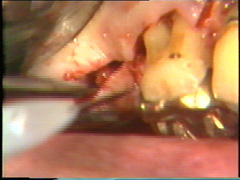

El colgajo se prepara permitiendo al escalpelo penetrar en el colgajo y moviendo lateralmente el cuchillo con un movimiento aserrado. El colgajo se extiende alrededor de 5-7 mm del area dónde se encontraba el colgajo originalmente. Para llevar a cabo dicha maniobra debe conocerse la anatomía de las estructuras adyacentes como los nervios, vasos y periodonto. |

Los restos de las papilas interdentales deben respetarse tanto como sea posible durante la modificación del colgajo. Los tejidos de la papila son necesarios para mejorar la cicatrización interdental y evitar la reabsorción osea interdental durante el procedimiento. |